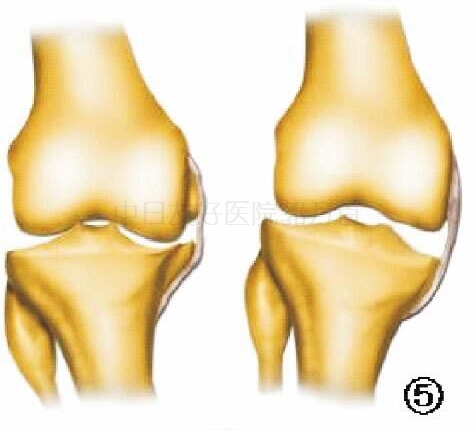

外翻应力示意图

X线片三:外翻应力

外翻应力X线可用来辅助评价外侧间室关节软骨厚度是否正常及内侧副韧带功能是否完整:①如果外侧间室关节间隙变窄提示外侧间室软骨磨损(约<5 mm),这是单髁关节置换的禁忌证。②如果内侧间室关节间隙分离大于等于5 mm,说明内侧副韧带没有短缩,即内翻可

充分矫正,如果外翻应力X线下内翻畸形不能有效矫正,内侧间室关节间隙仍然狭窄,说明内侧副韧带短缩,则单髁关节置换手术不适合。③如果外翻应力X线可以完全矫正内翻畸形及半脱位,可以选择单髁关节置换术。否则,不适合行单髁关节置。